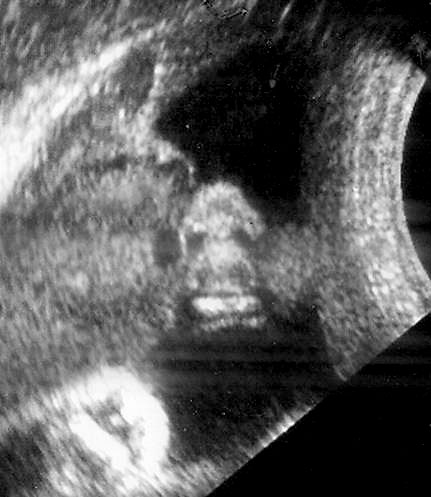

Normal nose and lips seen in coronal "swimmers view". - Sagittal view of face to visualize profile.

Normal sagittal view of fetal face.